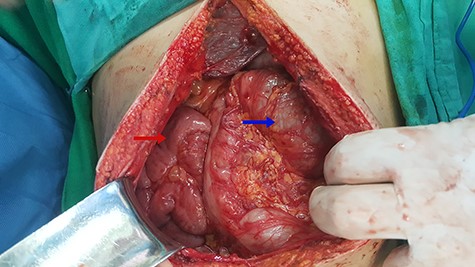

Laparoscopic surgery was excluded for technical and anatomical difficulties; we switched to open surgery. During intraoperative, we found malrotation (90° counterclockwise), where the small intestine was on the right side and the colons were on the left side (Fig. 2), and small intestine was slightly dilated and entrapped within a congenital hernia in the mesentery of the transverse colon (Fig. 3).

Small intestinal entrapped within a congenital transmesocolic hernia.